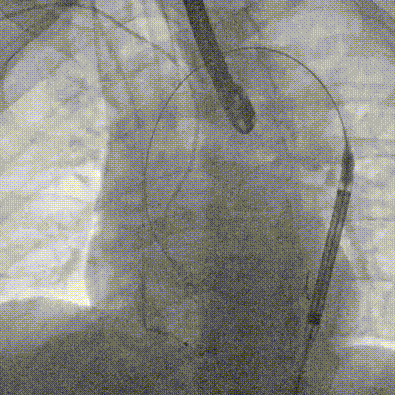

输送系统柔顺过弓

定位

迅速锚定释放至工作位

稳定脱钩

最终造影,位置形态良好